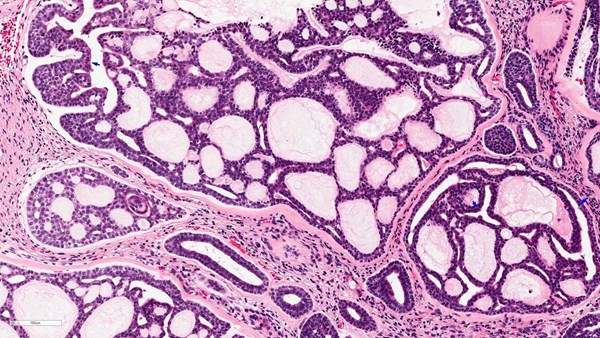

Salivary Gland Cancers

These are a rare group of cancers. They represent less than 5% of all head and neck malignancies and can also present in other areas of the body, including the windpipe, breast, skin and the vulva. Surgery, where possible, followed by radiotherapy is the most common treatment. Supporting research and clinical trials is vital to improve survival and reduce side effects in all patients.